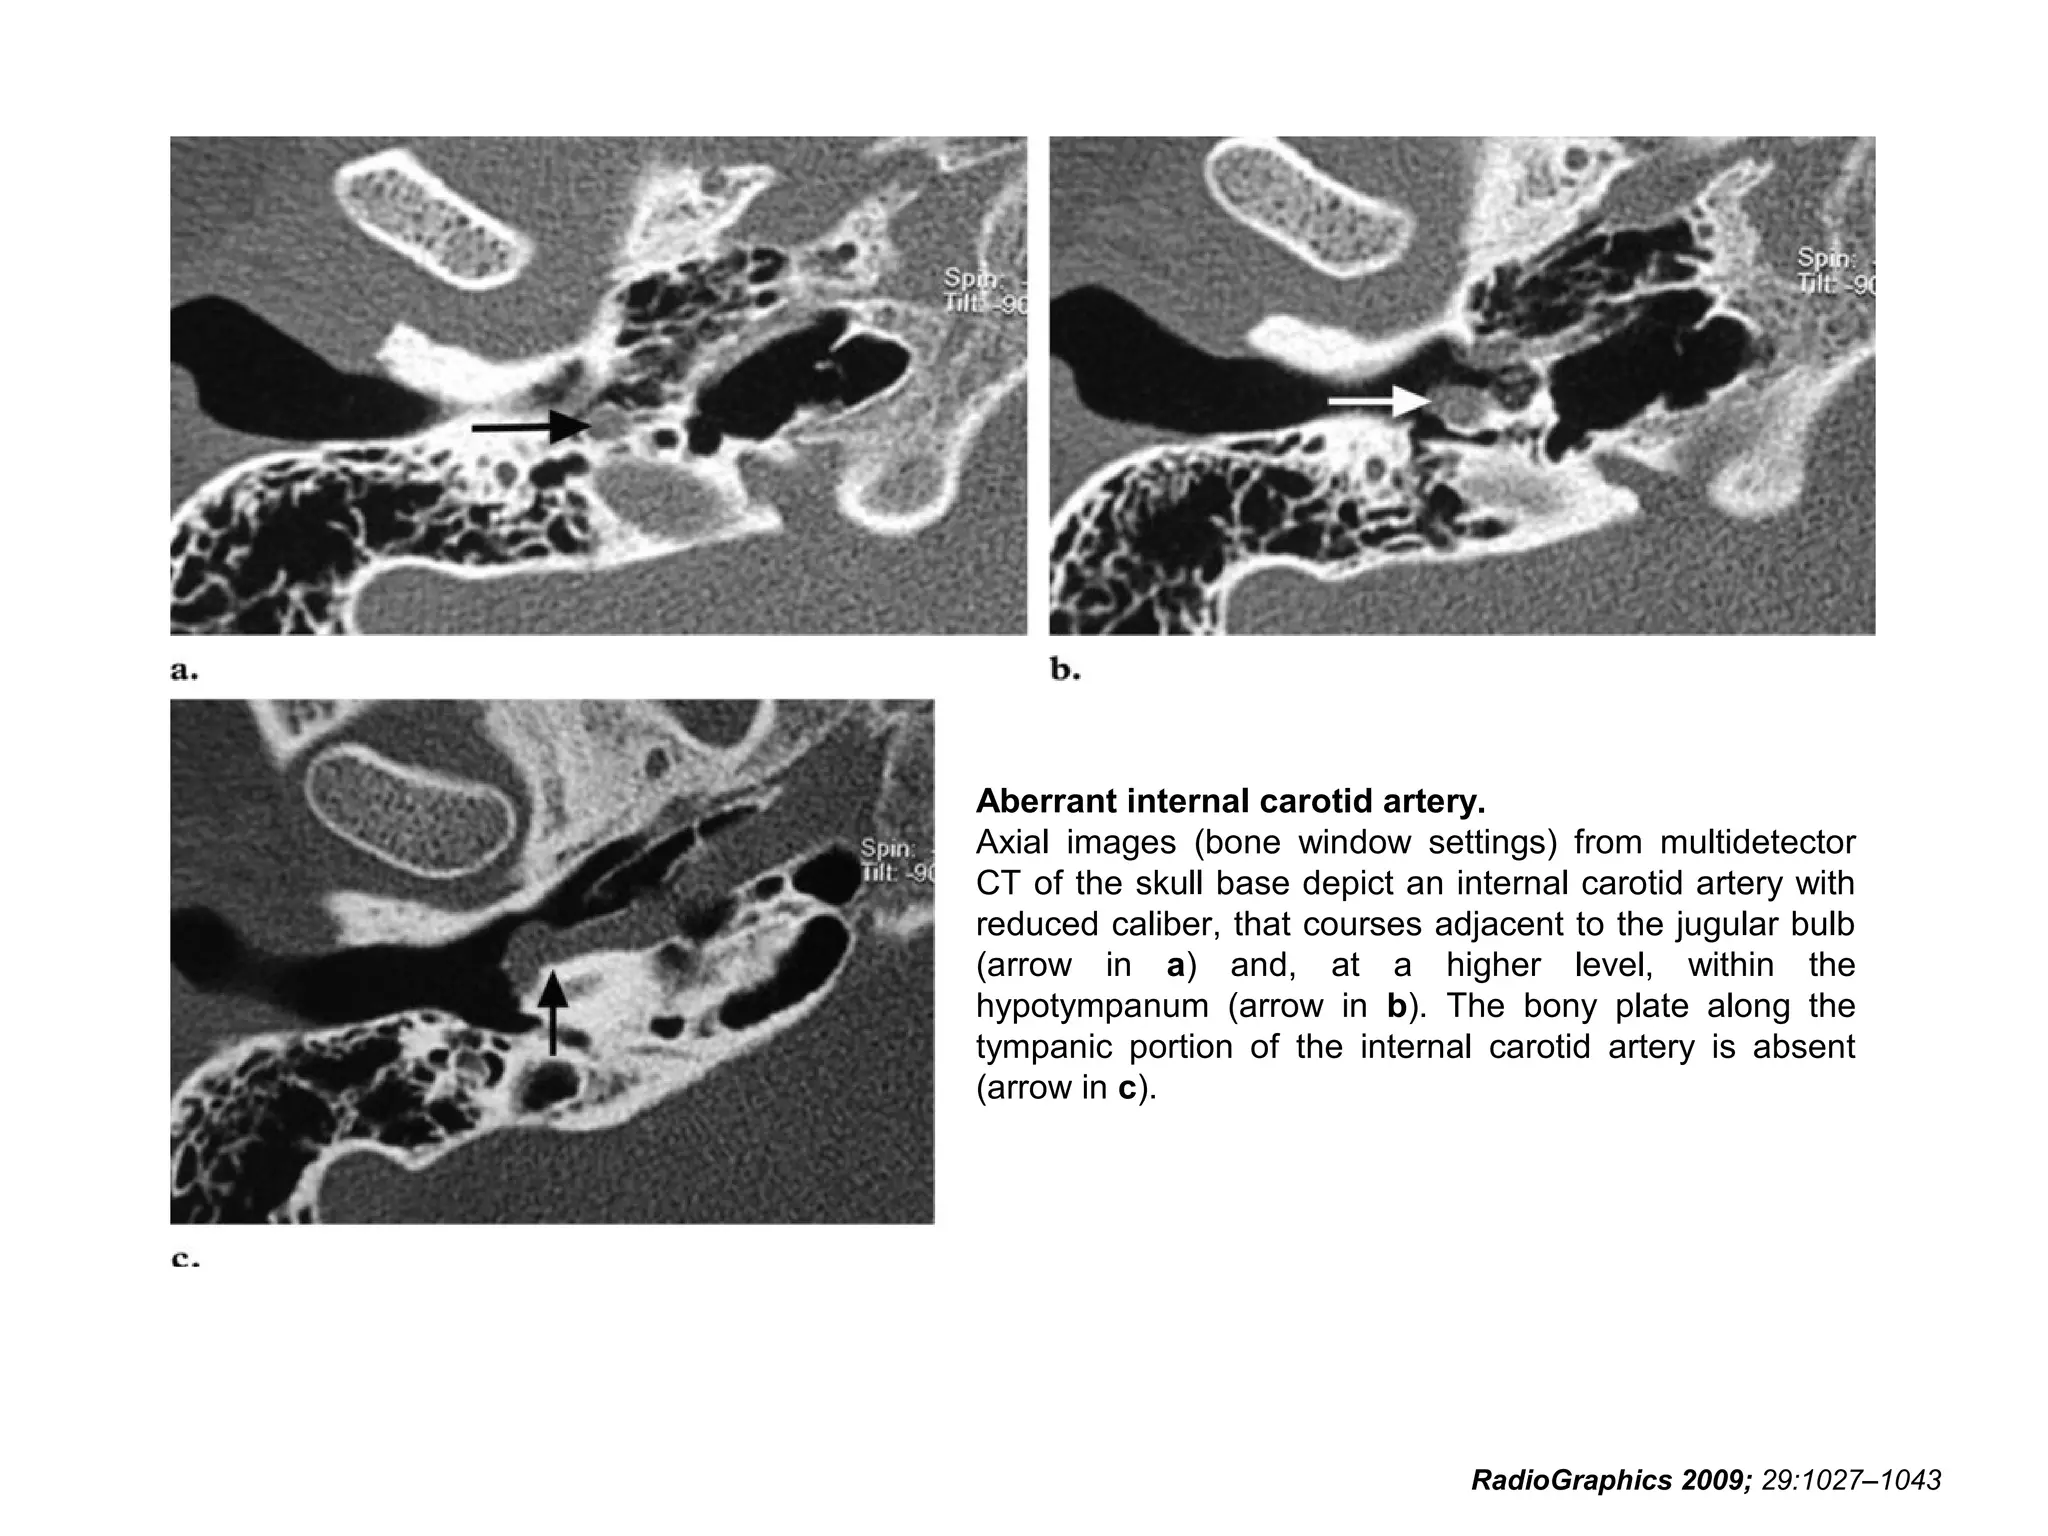

Aberrant Internal Carotid

Arteries

• Recognized aberrant internal carotid arteries

include intratympanic and lateral pharyngeal

variants.

• There are 50 previously reported cases of

aberrant intratympanic internal carotid artery in

the literature.

• This anomaly may be secondary to disturbed

differentiation of the third branchial artery.

• It is characterized by an enlarged inferior

tympanic artery that anastomoses with the

horizontal petrous part of the internal carotid

artery.

RadioGraphics 2009; 29:1027–1043

• On axial CT images, the presence of an aberrant

intratympanic internal carotid artery may be signaled by:

(a) an internal carotid artery with a reduced diameter

and a course posterior and parallel to the jugular bulb

(b) a mass in the hypotympanum

(c) deficiency of the bony plate along the tympanic

portion of the internal carotid artery

(d) absence of the vertical segment of the carotid canal.

Aberrant internal carotid artery.

Axial images (bone window settings) from multidetector

CT of the skull base depict an internal carotid artery with

reduced caliber, that courses adjacent to the jugular bulb

(arrow in a) and, at a higher level, within the

hypotympanum (arrow in b). The bony plate along the

tympanic portion of the internal carotid artery is absent

(arrow in c).

• 93.

Aberrant internal carotidartery. Axial images (bone window settings) from multidetector CT of the skull base depict an internal carotid artery with reduced caliber, that courses adjacent to the jugular bulb (arrow in a) and, at a higher level, within the hypotympanum (arrow in b). The bony plate along the tympanic portion of the internal carotid artery is absent (arrow in c). RadioGraphics 2009; 29:1027–1043